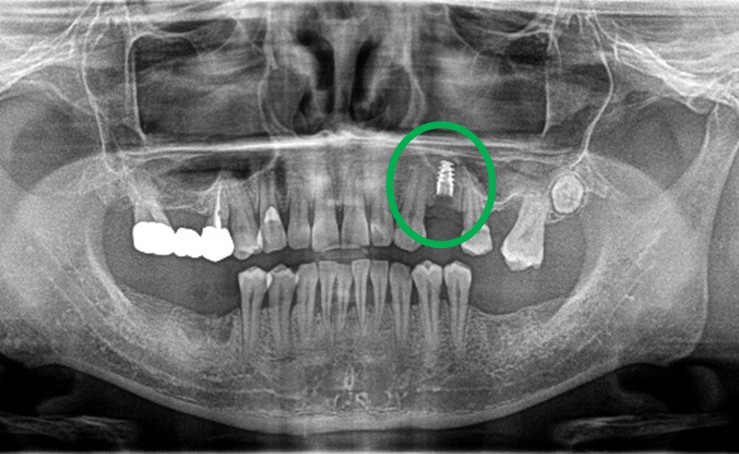

レントゲンで詳しく診てみると、虫歯が歯根のほうまで進行し、保存することができないことがわかり、抜歯しました。抜歯後、骨が大きく欠損していましたので、骨造成を行いインプラントを2本埋入しました。

抜歯後の欠損したところを補う方法には、部分入れ歯、ブリッジ、インプラントがあることを説明したところ、自分の歯と同じような感覚で嚙むことができるインプラントを選択されました。この方は、2016年に右下にインプラント治療をし、インプラントの良さを十分に理解しておられましたので、今回も2本歯を失ったところにインプラント治療を希望されました。今回もX-Guideを使った埋入で、安心安全に行うことできました。